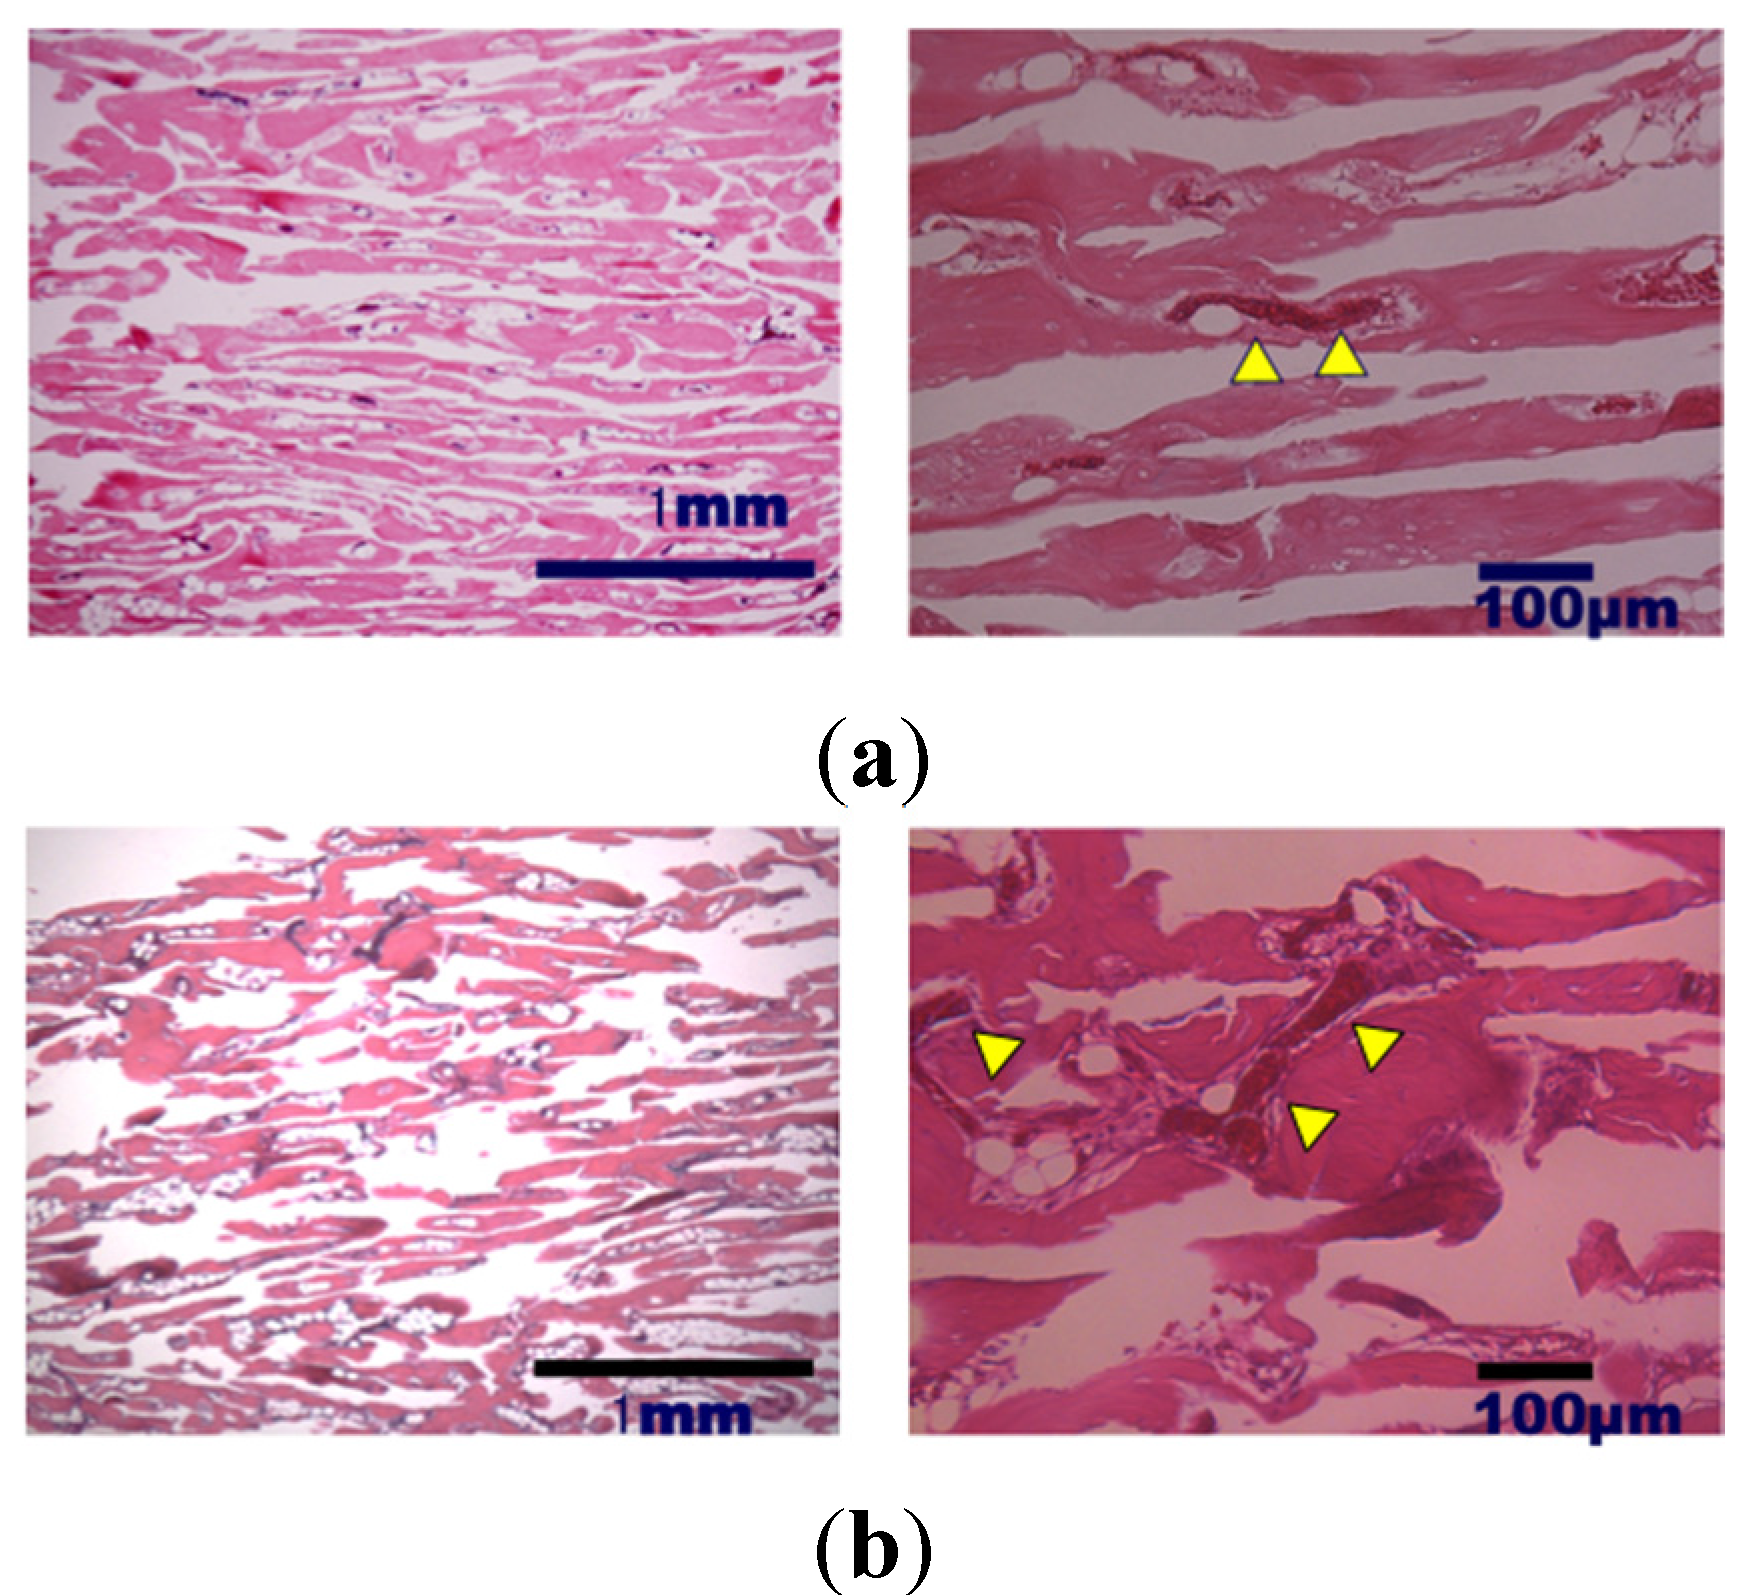

2. Results and Discussion

3.3. Bone Formation in Cortical and Medullary Bone Regions